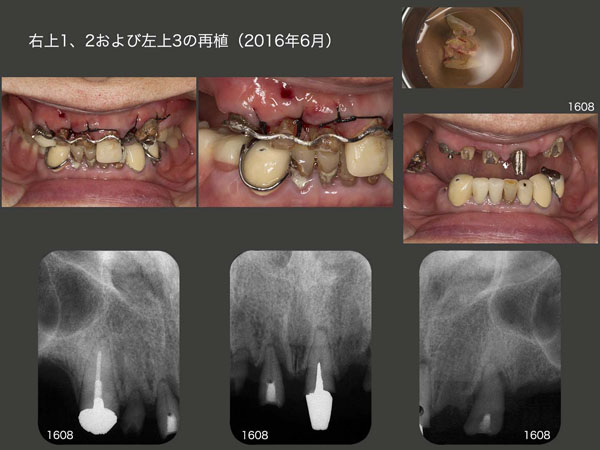

7.保存不可能と思われる歯を再植し、義歯の支台歯へ

2016年3月初診,79歳女性.右上3の冠がコアごと外れ,義歯が安定しなくなったとのことで来院.上顎においては残存歯をすべて抜歯し,総義歯にする選択肢があった.顎堤が優型であり,総義歯でも十分機能すると思われたが,口蓋を被うことになるので,異物感や発音障害が生じる可能性も考えられる等を説明したところ,患者さんはできるだけ歯を残して欲しいと希望した.

まず右上3の増歯を行い,つぎに同部の感染根管治療を行った.その後,暫間のOPAアタッチメントを装着し,義歯の維持を担ってもらった.なお,アタッチメント根面板の所に保持を設け,ワイヤーを固定できるように細工しておいた.

以上の準備が整ったところで,2016年6月に右上3および左上1を固定源として,右上1,2および左上3の再植を同時に行った.この際,歯肉縁上歯質が得られるところまで挺出し,ワイヤーに固定した.

デンタルX線写真は,術後2ヵ月半の状態であるが,右上2の動揺は収まらなかった.また左上3の遠心に7mmの歯周ポケットが残ったため,同部の歯肉切除を行った.

治療途中に骨折等で通院できず,治療期間は延びてしまったが,2017年12月に上下顎にコーヌス義歯を装着した.再植した右上2は動揺があるため側方力をかけないように根面板を装着するに留めた.左上3は若干の動揺があるため,少し丈の短い内冠を装着した.右上1は通常の長さの内冠を装着した.なお,3本の再植歯の歯周ポケットは3mm以下に落ち着いた.